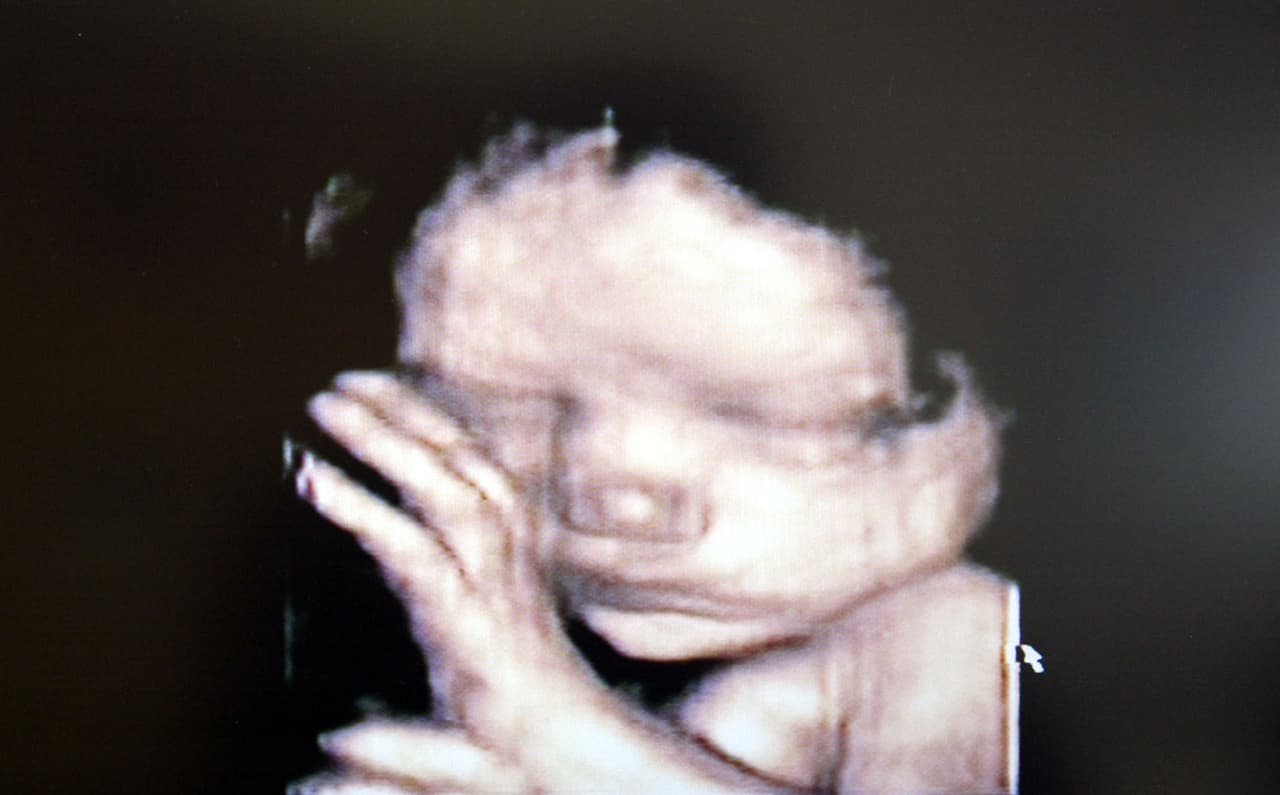

Mujer embarazada.

Imagen iStock